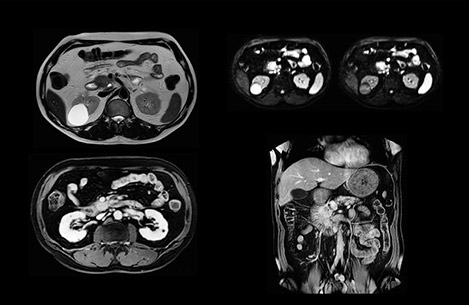

Comparison of liver MRI with and without MultiVane XD motion correction

In this example the image quality of the MultiVane XD images is evidently better than in the images without MultiVane XD. Ingenia 1.5T with dS Torso coil solution.

“We acquire one transversal high resolution T2-weighted sequence with 3 mm slice thickness, for example for pancreas or liver lesions. Then we also add a T2 fat suppressed MultiVane XD SPIR sequence. We perform these two routinely in our liver imaging. We use high dS SENSE factors to significantly shorten scan times to 2-4 minutes, which can improve our protocol; it’s a very robust scan.”